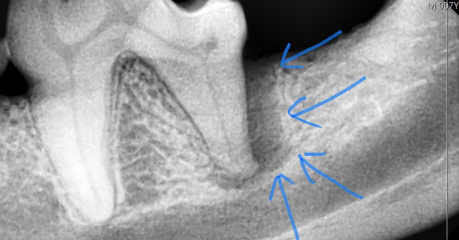

ラバーダム防湿

歯髄(歯の神経)を触る治療時の必須アイテムです。

人の歯科医院でも付加価値のある治療に使われています。

ゴムのシートを治療する歯に被せ、歯が唾液に触れることを防ぎます。

抜髄をする際にはラバーダム防湿を行うことで有害な洗浄液が正常組織に触れることを防ぎ、歯内をしっかりと洗浄殺菌できることから治療の成功率が上がります。

犬歯治療時の装着例

奥歯の装着例